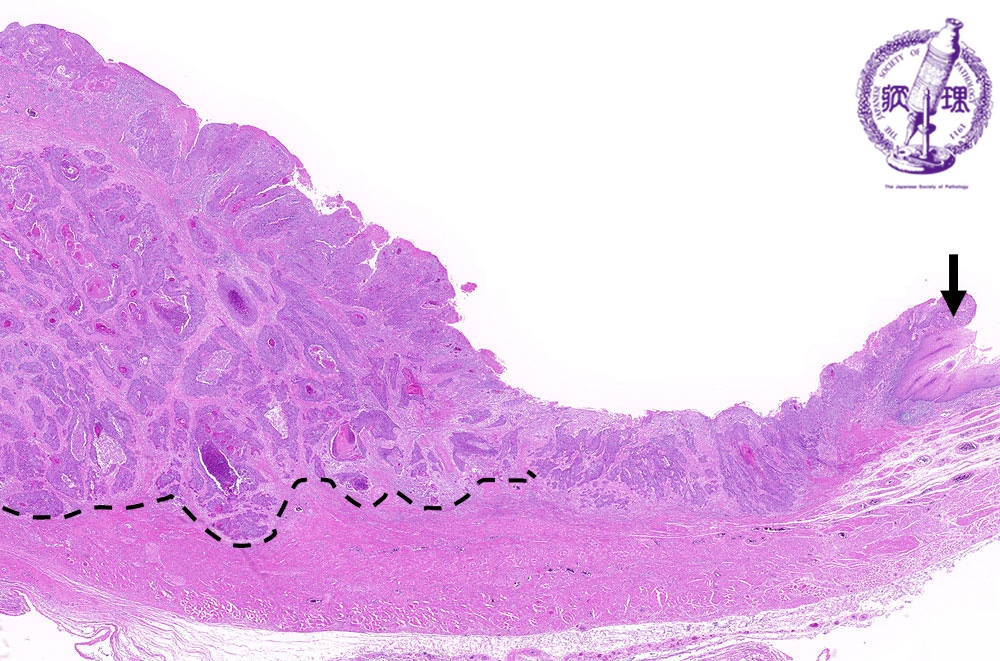

- ★(3)Esophageal carcinoma (squamous cell carcinoma)

Microscopic view (H&E stain, low power): There is squamous cell carcinoma invading into the muscularis propria (arrow: boundary between normal mucosa and carcinoma, dotted line: invasion into the muscularis propria).